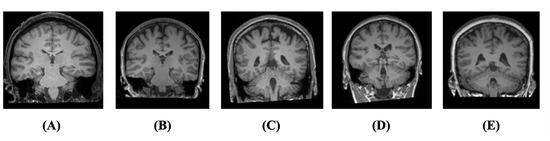

Figure 4.

Sample images of each age group of T1 brain MRI: (A) aged 20, (B) aged 30, (C) aged 40, (D) aged 50, and (E) aged 60.